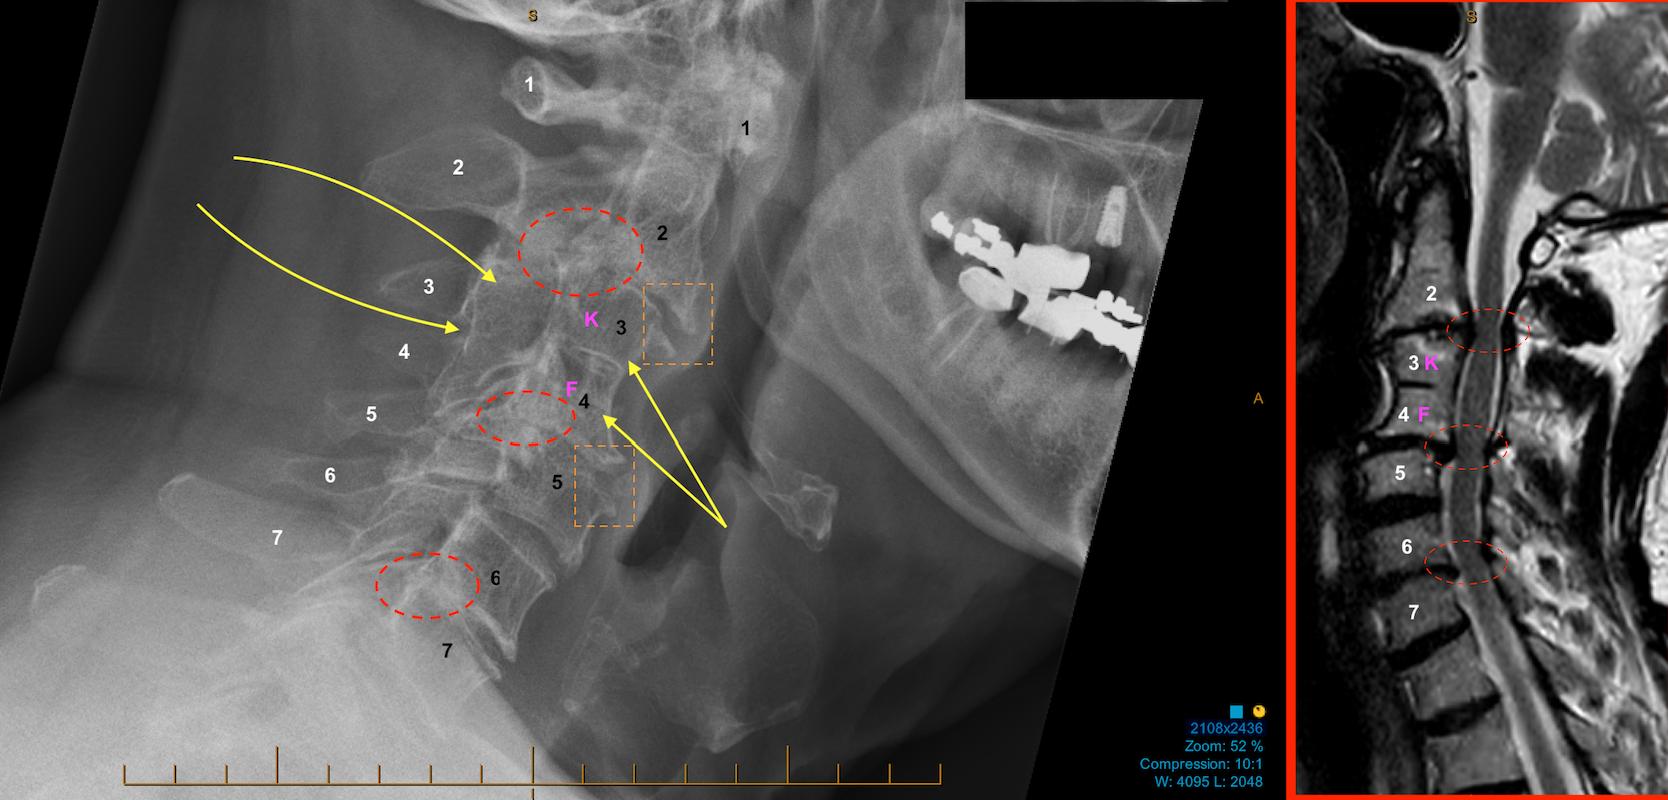

경추 6번과 7번이 붙어 있는 소견은 선천성 경추 유합(congenital cervical fusion)에 해당합니다. 배아 발생 과정에서 분절이 완전히 분리되지 않아 두 개의 척추체가 하나처럼 형성된 경우입니다. 일부는 Klippel-Feil spectrum에 포함되지만, 단일 분절 유합은 우연히 발견되는 경우도 적지 않습니다.

ㄴ Klippel Feil syndrome 환자의 증례로 경추 척추체가 붙어있는 모습을 볼 수 있습니다.

선천성 경추 유합은 전체 인구에서 약 0.5퍼센트 내외로 보고되며, C5–6, C6–7에서 발견되는 경우가 비교적 흔합니다. 다만 대부분은 무증상으로 지내다가 영상 촬영 중 우연히 확인됩니다.